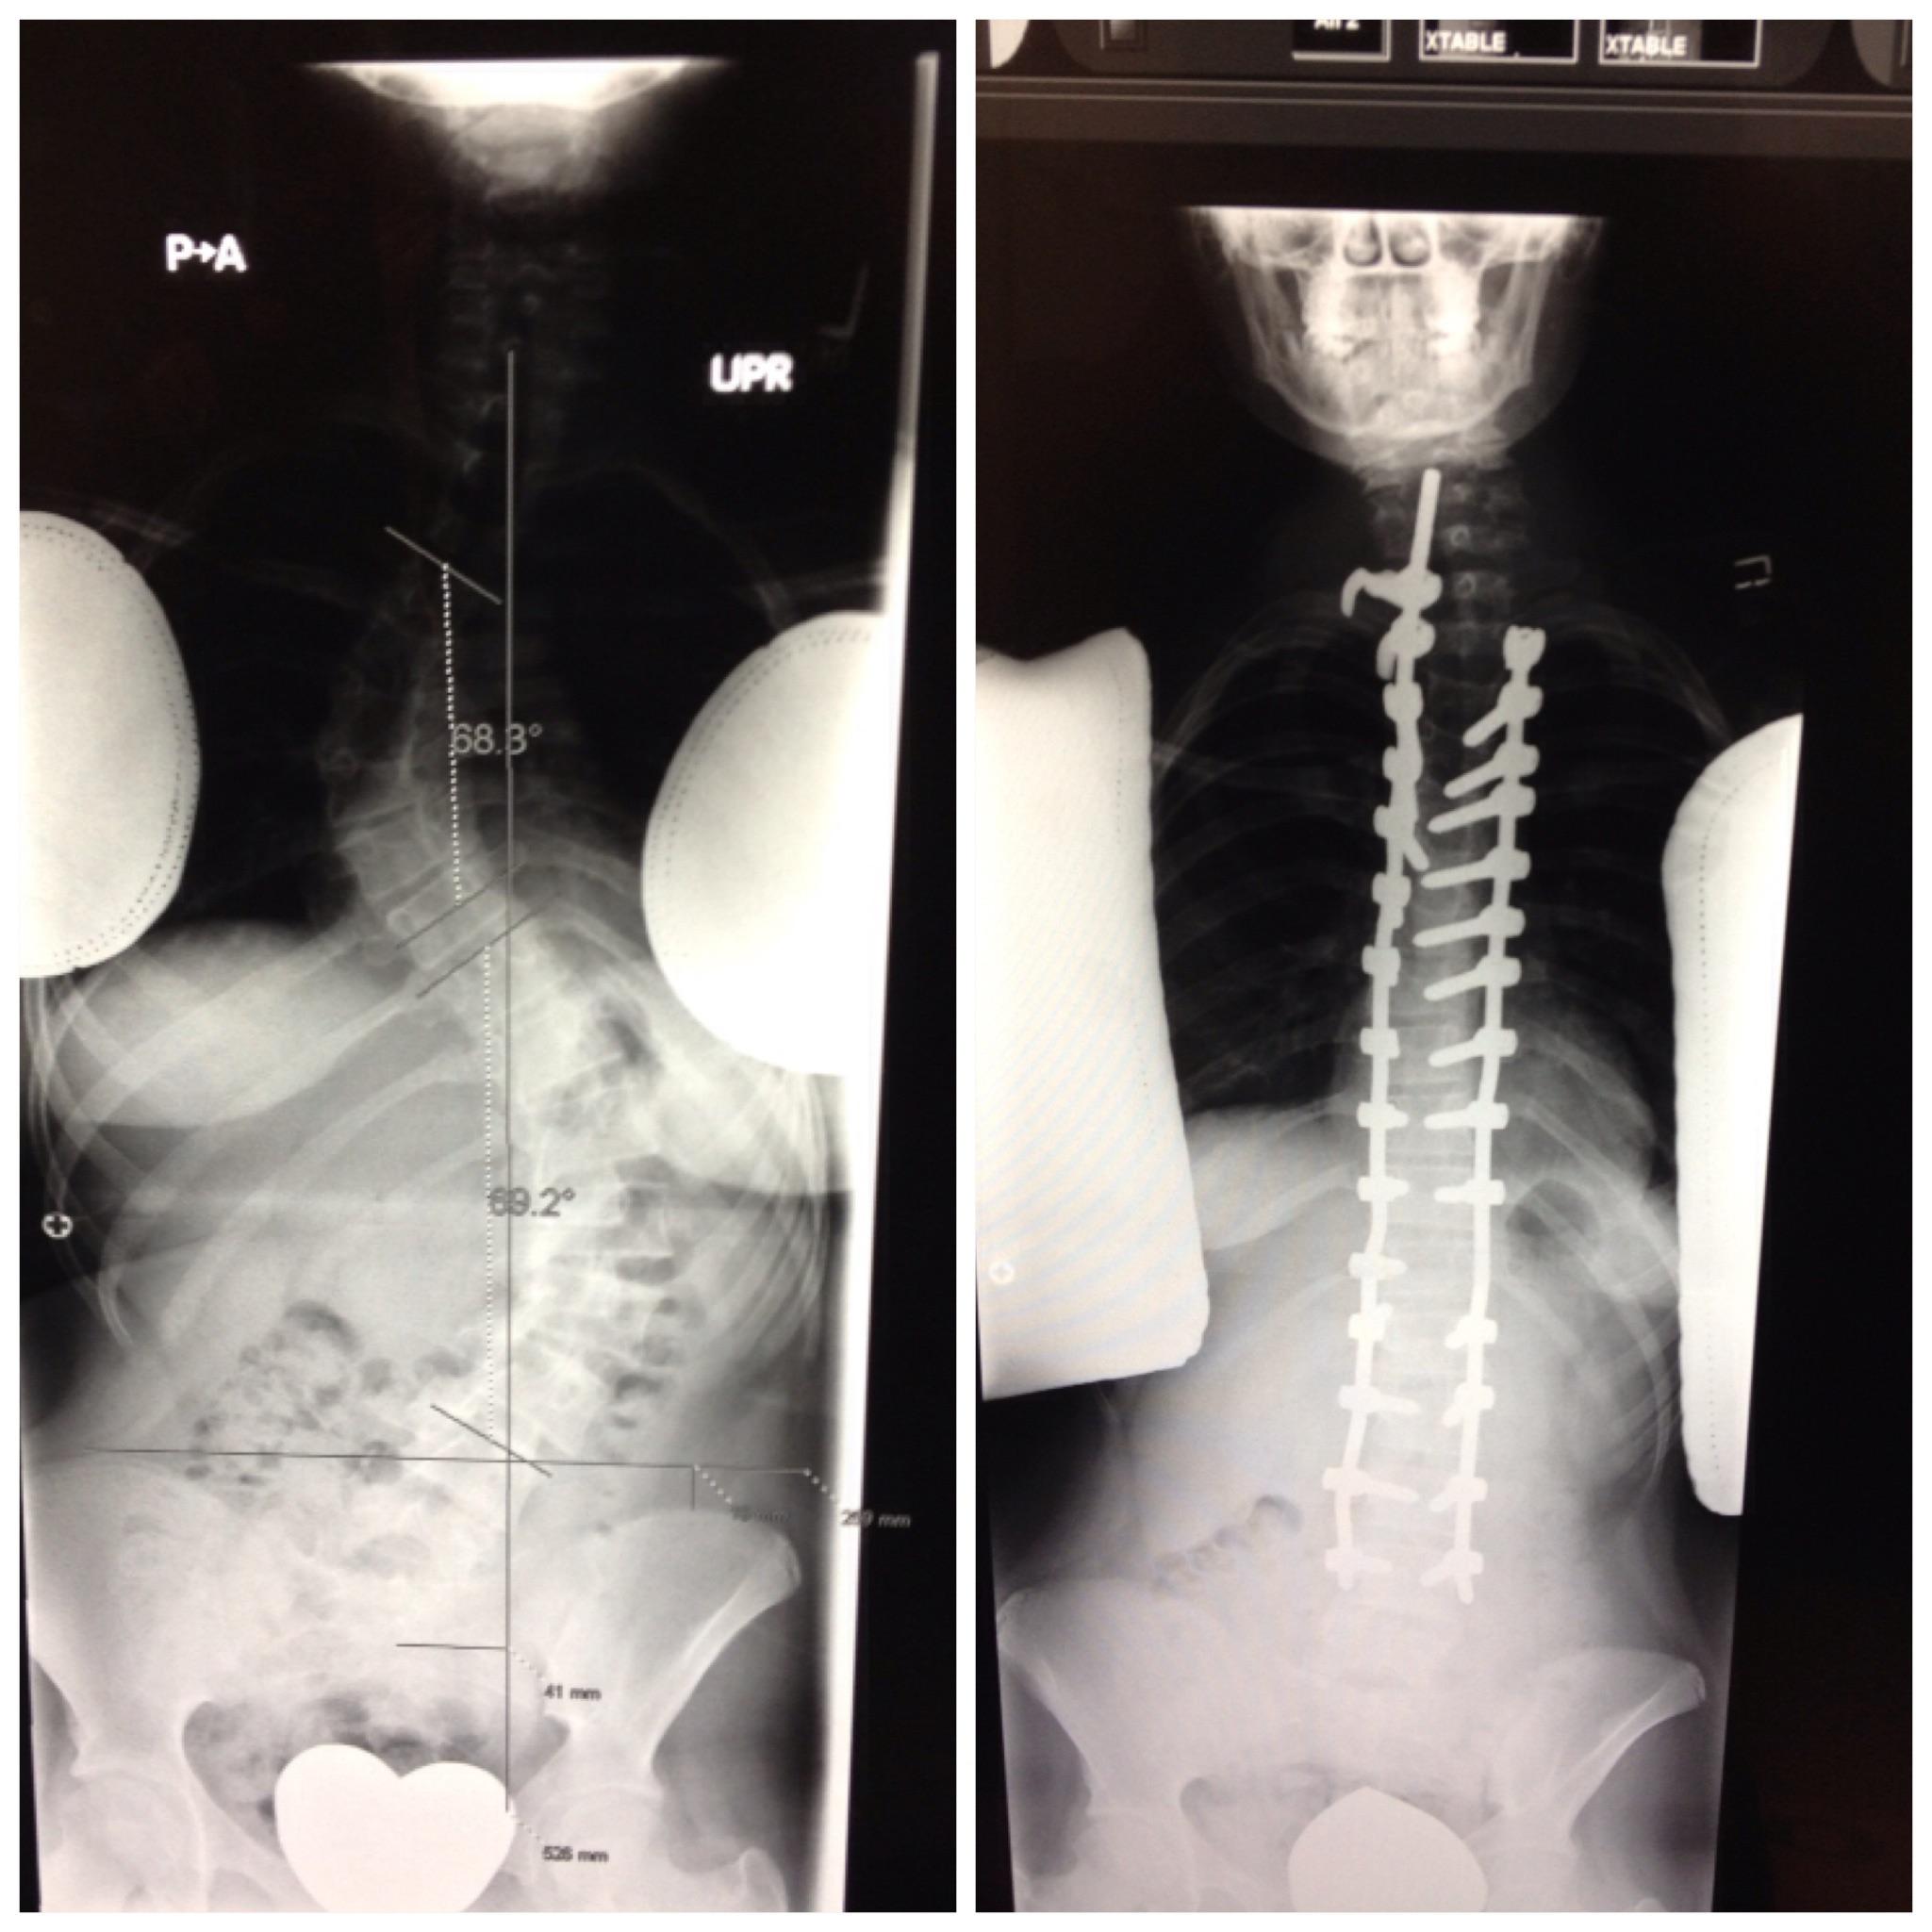

From www.reddit.com

Can this be fixed with scroth I want a straight spine r/scoliosis Can My Scoliosis Be Fixed For more severe scoliosis, families now have treatment options. You can have scoliosis without experiencing severe symptoms, or you could require surgery. Spinal fusion is the most common method for surgically correcting scoliosis. The way to deal with your scoliosis depends on how severe the curve of your back is. Treatment may include observation, a brace or. The goal of. Can My Scoliosis Be Fixed.

From journal.medizzy.com

Scoliosis surgery, before and after. MEDizzy Journal Can My Scoliosis Be Fixed Spinal fusion is the most common method for surgically correcting scoliosis. Most people with scoliosis can participate in physical activities and exercise. Volume 90% adult scoliosis treatment options at mayo clinic. Fortunately for most adults who have scoliosis, the condition can be successfully managed without surgery. Routine movement can reduce the severity of. You can have scoliosis without experiencing severe. Can My Scoliosis Be Fixed.

I had a complete Posterior Spinal Fusion in December 2012 to fix my severe scoliosis and grew 4 Can My Scoliosis Be Fixed The way to deal with your scoliosis depends on how severe the curve of your back is. For more severe scoliosis, families now have treatment options. Volume 90% adult scoliosis treatment options at mayo clinic. Spinal fusion is the most common method for surgically correcting scoliosis. You can have scoliosis without experiencing severe symptoms, or you could require surgery. Ongoing. Can My Scoliosis Be Fixed.

From www.spineandscoliosis.com

Before and After Scoliosis Surgery with Darryl Antonacci Can My Scoliosis Be Fixed Spinal fusion is the most common method for surgically correcting scoliosis. Volume 90% adult scoliosis treatment options at mayo clinic. Treatment may include observation, a brace or. The goal of this surgery is to realign the curved areas of the spine, fusing metal rods or. Find out how your doctor will watch the progression of your scoliosis and when. For. Can My Scoliosis Be Fixed.